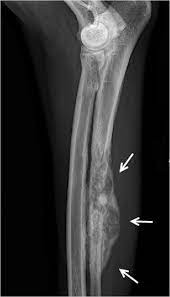

Osteosarcoma Most Common Primary Bone Tumor In Dogs All Current Therapies from www.vetcontact.com Dog bone cancer, also called osteosarcoma, occurs in about 5% of all tumors in dogs. Radiation is a common method for the palliation of bone cancer pain in human and animal cancer patients. Amputation provides definitive pain relief. The changes characteristic of bone cancer can be seen fairly early on. Approximately 85 percent of canine bone tumors are osteosarcomas ( osteo = bone, sarcoma = cancer ). In 2010, bone cancer dogs, inc. In a recent study in four dogs with osteosarcoma, pain relief from hypertrophic osteopathy was observed in all dogs less than 24 hours after metastasectomy.15 peripheral and central neuroablative surgeries can be contemplated in select cases; Pain is a problem for dogs with cancer because it causes such life quality loss.that's why recognizing when your dog is in pain, and finding a way to control dog cancer pain, is a very important part of full spectrum cancer care.